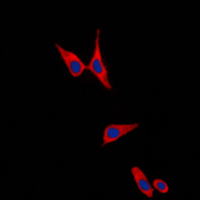

Immunofluorescent analysis of E Cadherin staining in PC12 cells. Formalin-fixed cells were permeabilized with 0.1% Triton X-100 in TBS for 5-10 minutes and blocked with 3% BSA-PBS for 30 minutes at room temperature. Cells were probed with the primary antibody in 3% BSA-PBS and incubated overnight at 4 °C in a humidified chamber. Cells were washed with PBST and incubated with a DyLight 594-conjugated secondary antibody (red) in PBS at room temperature in the dark. DAPI was used to stain the cell nuclei (blue). -